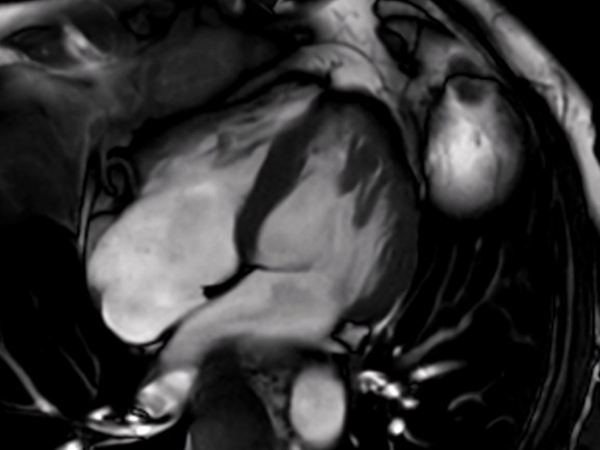

Comprehensive Cardiac with SmartSpeed Precise